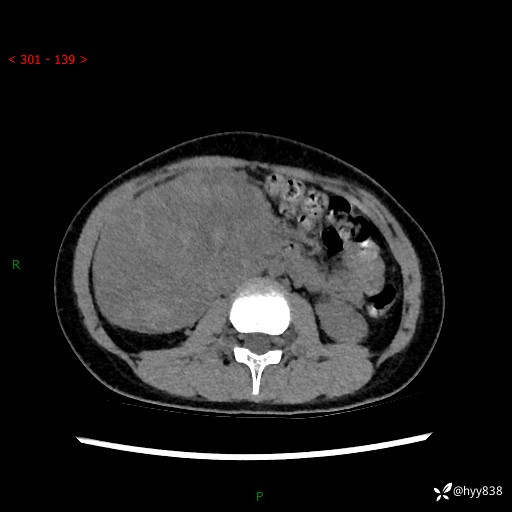

病例小姑娘,超声提示上腹部巨大包块。平扫就能轻松搞定的病变--结果公布

性别:女

年龄:13岁

简要病史:超声提示上腹部巨大包块

上腹部CT平扫

胰腺实性假乳头状瘤 (17)